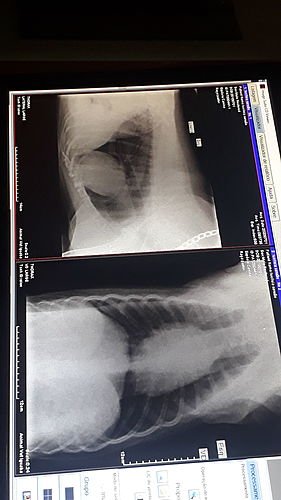

Olá pessoal, meu irmãozinho, Sansão, foi diagnosticado com osteossarcoma e precisará realizar uma cirurgia de amputação da patinha onde está localizado o tumor.No momento estamos sem condições de arcar com os custos da cirurgia. Já realizamos os exames de raio x da área afetada e do pulmão e coração para saber se há metástase ou não, e graças a Deus, não há metástase. Estamos tratando da dor que essa doença causa com medicamentos prescritos pelo veterinario. Ele tambem esta tomando um suplemento vitamínico para impedir a evolução da doença.

Sobre o Sansão: Sansão tem 10 aninhos e sempre foi um cachorrinho muito alegre, ativo, carinhoso, que ama correr e andar de carro pegando um ventinho na janela. Porém, de uns tempos pra cá ele começou a mancar muito. Levamos ele ao veterinário, que pediu pra fazer o exame de Radiografia, onde ele foi diagnosticado com essa doença, o osteossarcoma. Ele está sendo medicado para dor, mas não é mais o mesmo, ele ama passear, mas até em nossos passeio ele fica aparentemente triste, tudo por conta da dor. Ele é o MELHOR cachorro que eu conheci e tenho o prazer de conviver e não suporto vê-lo sofrer tanto assim. Sobre o tumor ósseo (osteossarcoma): O osteossarcoma é um tumor maligno ósseo que é mais notado em cães. Esse tipo de anomalia é caracterizado por acometer diferentes órgãos e regiões do corpo do animal, sendo bem agressivo e doloroso. A terapia que é mais usada nesse tipo de tratamento é na amputação seguida de quimioterapia uma vez que melhora bastante os resultados.Podem me solicitar os comprovantes de gastos, envio de fotos, vídeos e qualquer outro tipo de confirmação ou informação, deixo meu número de WhatsApp: (21) 971928043 pra contato.Toda ajuda é SUPER bem vinda, serei eternamente grata.